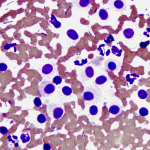

ציטולוגיה